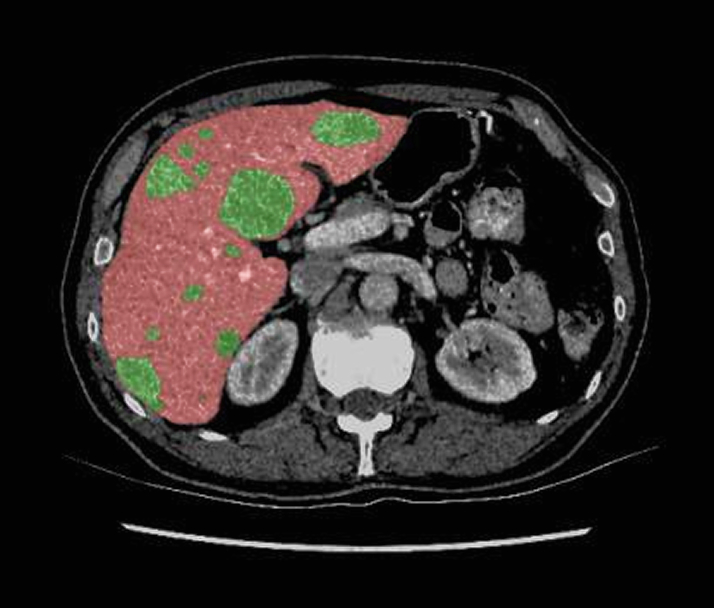

3D image segmentation is revolutionizing the way clinicians and researchers understand the human body. By transforming 2D medical images into precise 3D models, this technology enables deeper anatomical insights, enhances diagnostic accuracy, and streamlines surgical planning. At the forefront of AI-driven healthcare innovation, segmentation serves as the foundation for effective treatment, data-driven decisions, and scalable clinical research.

3D image segmentation, a technique that isolates anatomical regions from MRI, CT, or ultrasound, is foundational in clinical diagnosis, treatment planning, and quantitative analysis. When applied in 3D, it enables:

- Quantitative analysis through volumetric measurements of organs or lesions is crucial for tracking disease progression and therapy effectiveness.

- We combine clinician expertise and advanced annotation tools to efficiently annotate 3D medical volumes, cutting annotation labor while preserving accuracy.